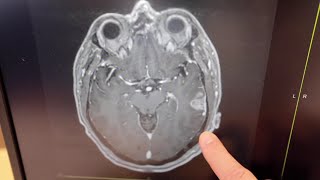

New results show vaccine could help fight brain cancer

New results show vaccine could help fight brain cancer Vaccine has promising results in the fight against a deadly form of brain cancer

Vaccine has promising results in the fight against a deadly form of brain cancer Trials show experimental cancer vaccine may slow growth of brain tumors

Trials show experimental cancer vaccine may slow growth of brain tumors Cancer vaccine to simultaneously kill and prevent brain cancer developed

Cancer vaccine to simultaneously kill and prevent brain cancer developed Lifespan to announce results of vaccine trial for aggressive brain cancer

Lifespan to announce results of vaccine trial for aggressive brain cancer New Vaccine For Deadly Brain Cancer Shows Incredible Result in Clinical Trial! How It Works!